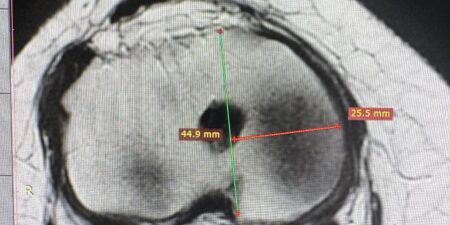

Un intervento chirurgico programmato con il supporto dell’intelligenza artificiale è stato eseguito con successo all’ospedale Ospedale Di Venere di Bari. Lo ha reso noto la Asl Bari, spiegando che si tratta del primo intervento di riparazione endovascolare di aneurisma dell’aorta addominale pianificato attraverso sistemi di analisi predittiva e tecnologia “Digital Twin”, il cosiddetto “gemello digitale”. […]

Dopo sei anni di stop, la cardiochirurgia pediatrica dell’ospedale Ospedale Giovanni XXIII di Bari continua il percorso di ripartenza. Nei giorni scorsi sono stati eseguiti con successo altri due interventi su piccoli pazienti affetti da gravi malformazioni cardiache congenite. Il primo intervento ha riguardato un bambino di 7 anni sottoposto a un’operazione cardiochirurgica per correggere […]